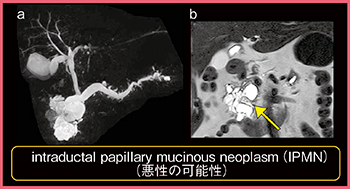

●膵MRI(MRCP)

当院では,膵臓のMRI検査もすべてTRILLIUM OVALで行っている。囊胞性膵腫瘍の良悪の判断において,囊胞内に充実性部分があるか,膵管と連続しているか,また膵管がどれだけ拡張しているかを評価することが重要である。

TRILLIUM OVALによるMRCP(図5 a)では,膵頭部の多房性の囊胞性病変や分枝膵管が明瞭に描出されている。本症例では,T2強調画像の冠状断にて囊胞内部に低信号(図5 b←)を確認でき,充実性部分の存在が疑われる。悪性合併の可能性があるintraductal papillary mucinous neoplasm(IPMN)が疑われたが,患者の希望により経過観察となっている。

図5 MRCP画像